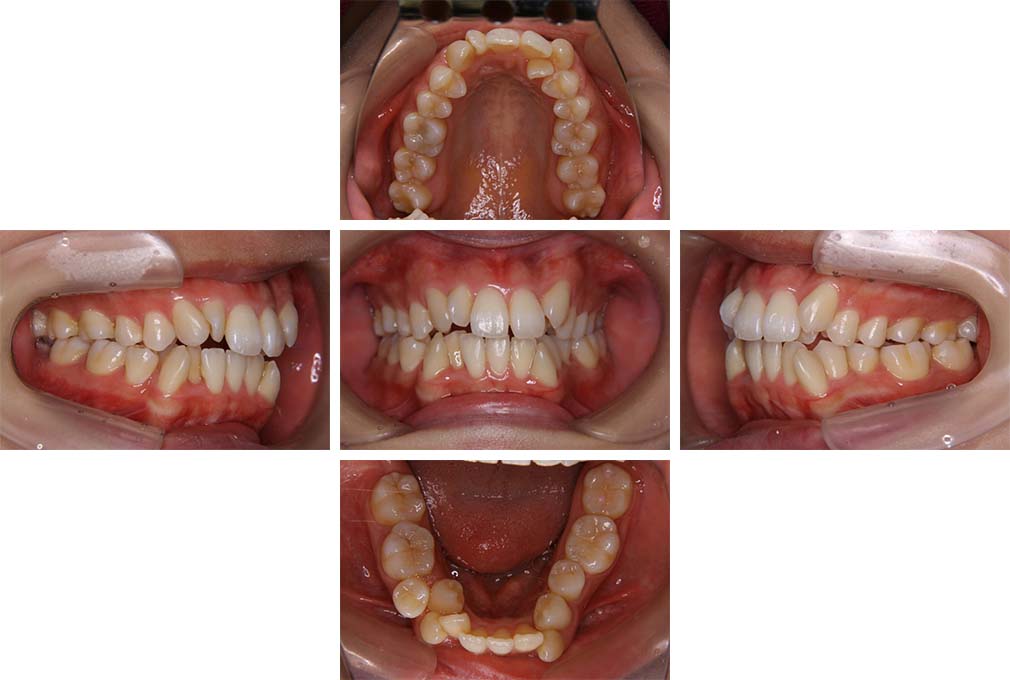

CASE:01

叢生を伴う骨格性上顎前突

初診時年齢 15歳10カ月

性別 男性

治療費の目安 約75万円程度(治療開始時)

上顎前歯の前突と叢生を主訴として来院された。大臼歯関係は左右側ともにⅡ級で上顎の方が前方に位置していた。叢生を伴う骨格性上顎前突と診断し、上下顎小臼歯抜歯を行っていただきマルチブラケット装置に顎外固定装置を併用して動的治療を行った。顎外固定装置や矯正用ゴムの使用など協力状態も良好で、動的治療期間2年0カ月、調整来院20回でマルチブラケット装置を撤去し保定へ移行した。動的治療終了後10年0カ月を経過したが保定移行時とほぼ同様の咬合状態で良好な状態を保っていた。

治療前

15歳10か月

治療後

動的治療期間2年0カ月

18歳5か月

10年経過

動的治療終了後10年0カ月

28歳5か月